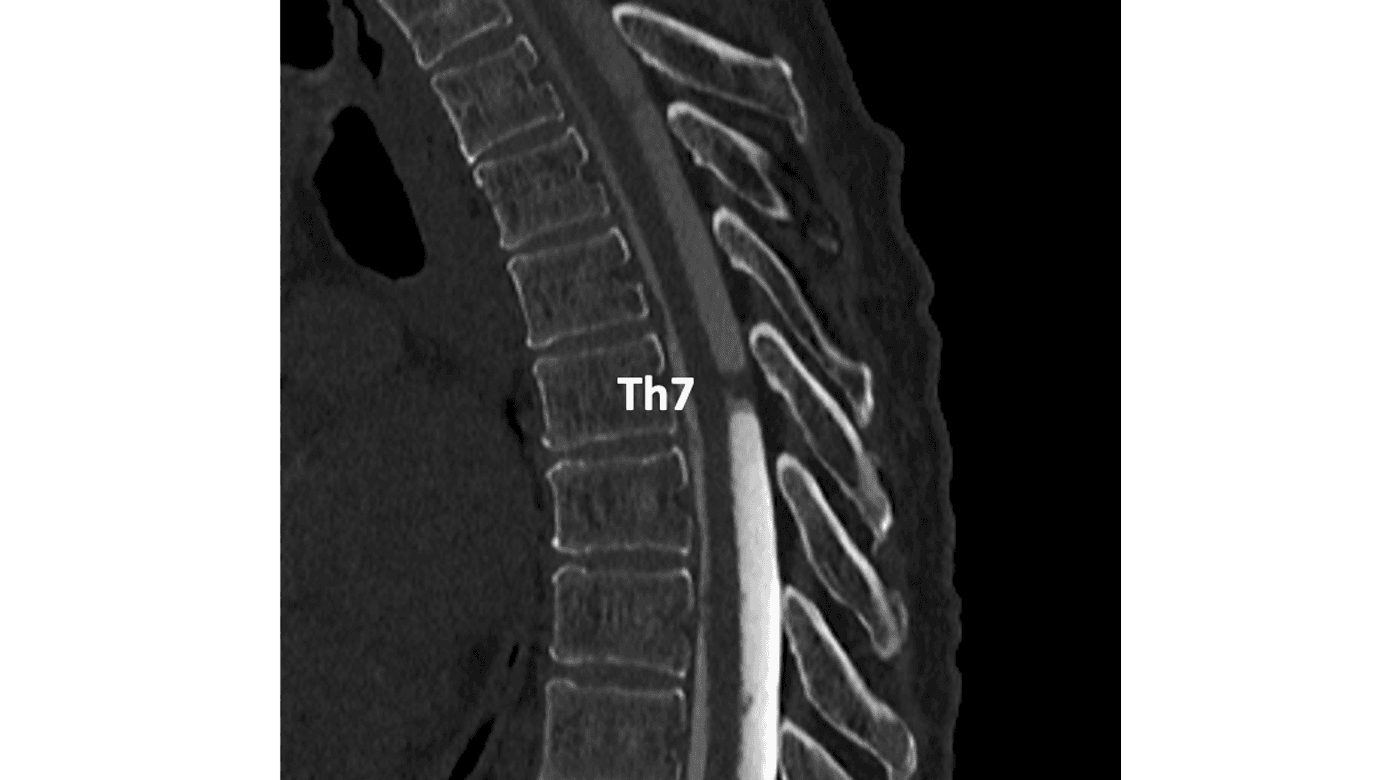

MR-skanning af medulla spinalis blev beskrevet med pial siderosis, men uden nogen påvist blødningskilde, og man gik videre med CT-myelografi, der viste udfyldning i dura mater spinalis ved Th7 (Figur 1B og C).